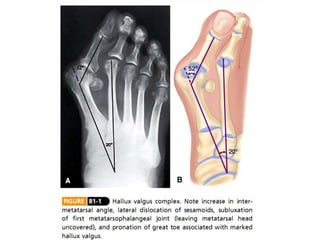

Angulo del hallux valgus (15 -20°)

Angulo intermetatarsal (8-9°)

Angulo articular metatarsal distal (DMMA) (10-15°)

Congruencia articular

Cambios degenerativos

Primera unión MTT-falange

Longitud del 1° - 2° metatarso

Posición del sesamoideo

Osteotomía en Vinvertida Hallux valgus angle Intermetatarsal angle Distal metatarsal articular angle

Angulo del halluxvalgus (15 -20°) Angulo intermetatarsal (8-9°) Angulo articular metatarsal distal (DMMA) (10-15°) Congruencia articular Cambios degenerativos Primera unión MTT-falange Longitud del 1° - 2° metatarso Posición del sesamoideo